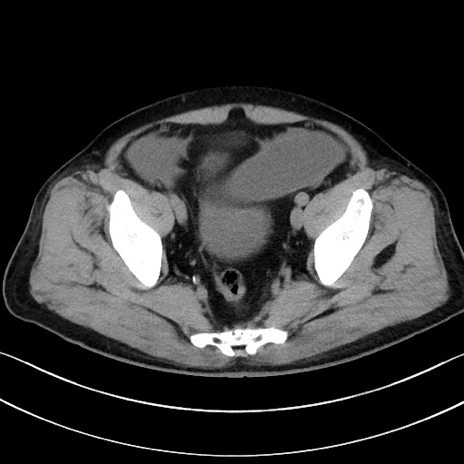

症例15(横断像)

【症例】70歳代男性

【主訴】腹痛

【現病歴】今朝から腹痛あり。全体的に痛い。特に左上の方。排ガスが今日はない。冷や汗が出る。

【既往歴】直腸癌術後

【身体所見】左側腹部〜上腹部に圧痛あり。腹膜刺激症状明らかなではない。軽度反跳痛。左下腹部に術後瘢痕あり。

【データ】WBC 7700、CRP 0.02